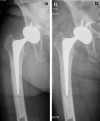

Background: Dual mobility implants are subject to a specific implant-related complication, intraprosthetic dislocation (IPD), in which the polyethylene liner dissociates from the femoral head. For older generation designs, IPD was attributable to late polyethylene wear and subsequent failure of the head capture mechanism. However, early IPDs have been reportedly affecting contemporary designs.

Results: In all, 16 articles met our inclusion criteria. Fourteen were case reports and 2 were retrospective case series. These included a total of 19 total hip arthroplasties, which were divided into 2 groups: studies dealing with early IPD after attempted closed reduction and those dealing with early IPD with no history of previous attempted closed reduction. Early IPD was reported in 15 patients after a mean follow-up of 3.2 months (2.9 SD) in the first group and in 4 patients after a mean follow-up of 15.1 months (9.9 SD) in the second group.

Conclusions: Based on the current data, most cases have been preceded by an attempted closed reduction in the setting of outer, large articulation dislocation, perhaps indicating an iatrogenic etiology for early IPD. Recognition of this possible failure mode is essential to its prevention and treatment.